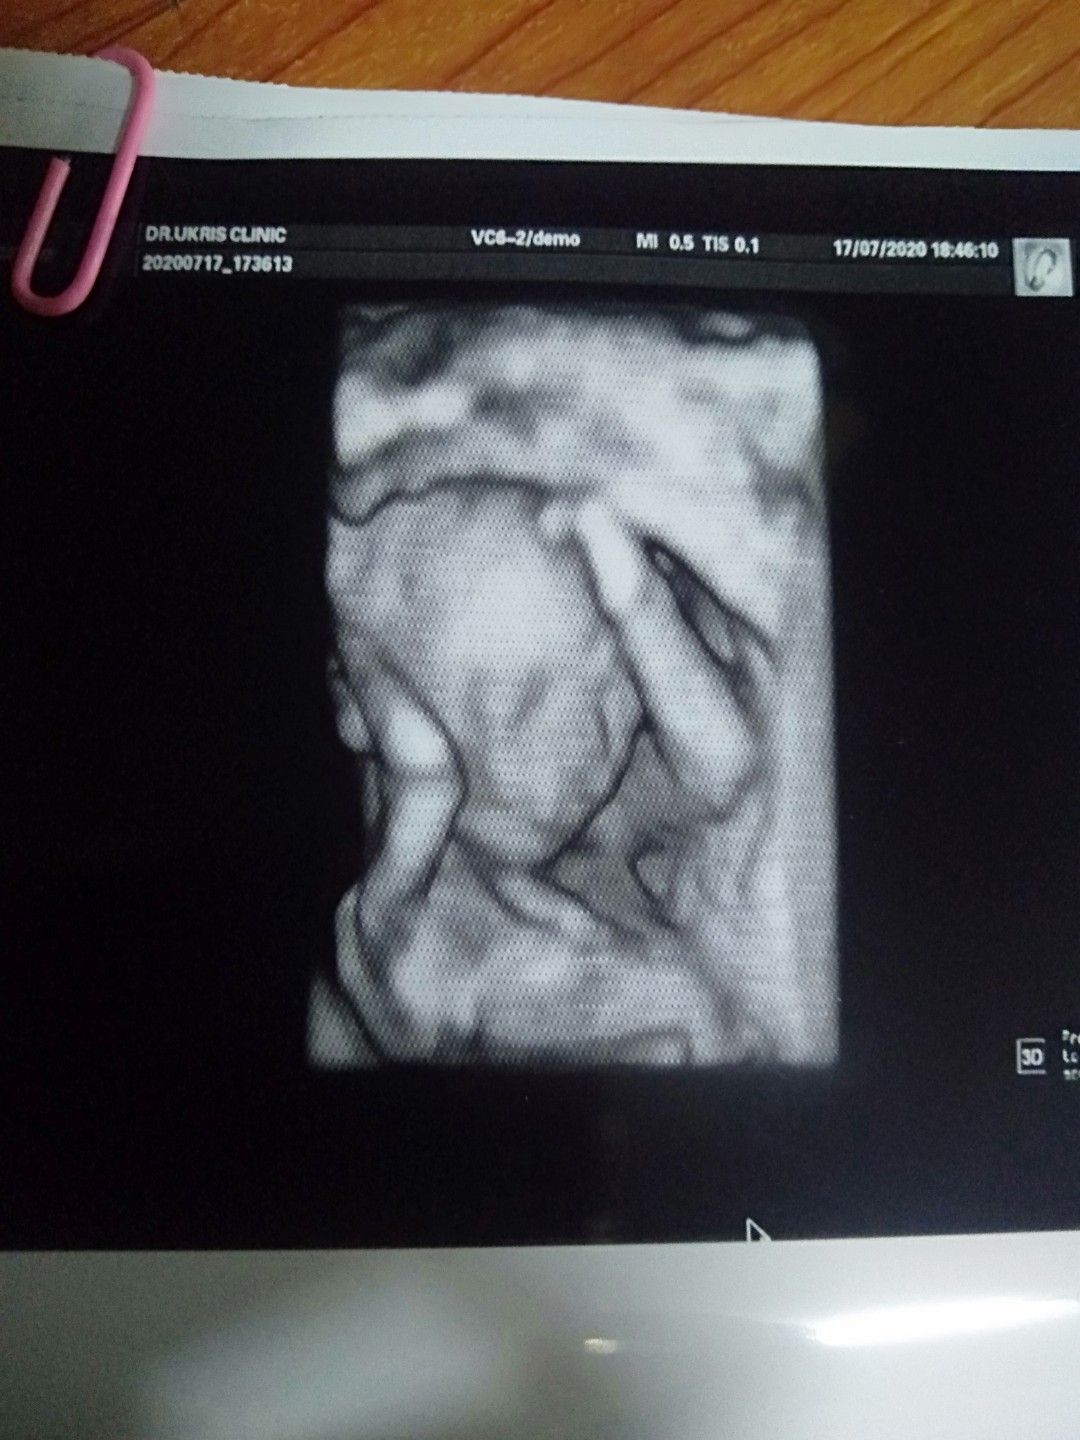

20 Week ได้ลูกชายค่ะ 🥰🥰

20w ลูกชายค่ะ👼